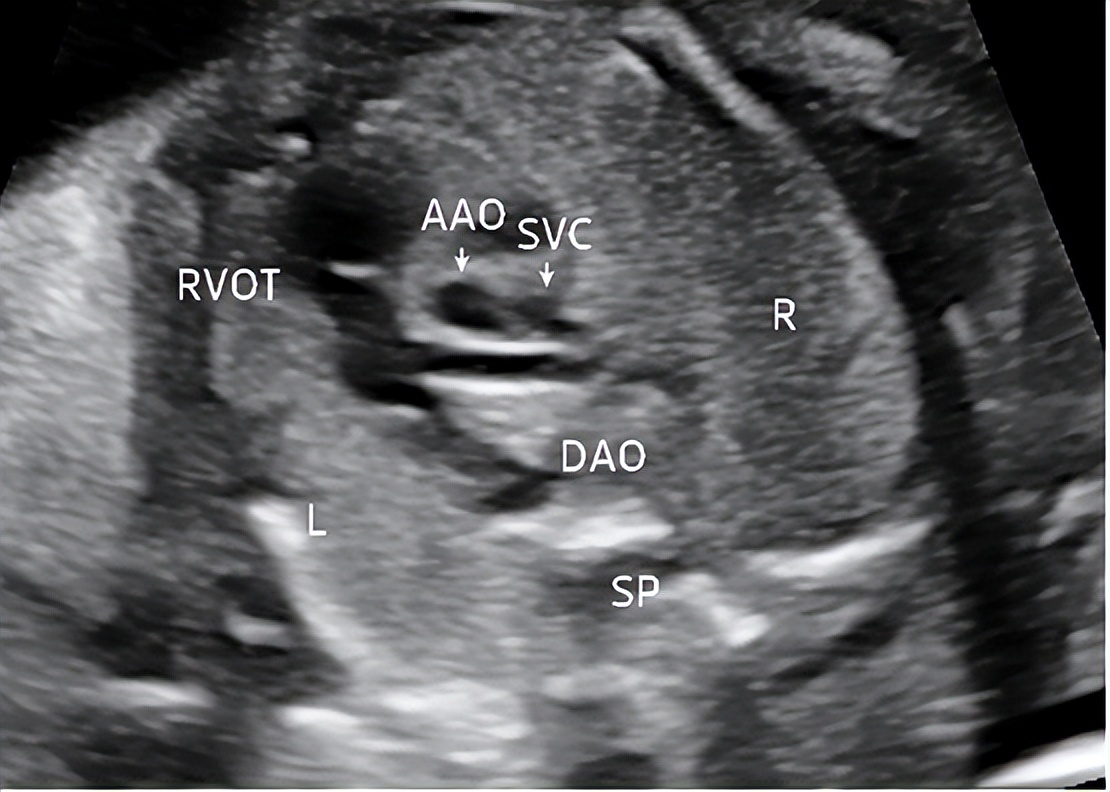

3.右心室流出道切面

切面要求:显示右心室及起自右心室的肺动脉和肺动脉瓣(图3)。

观察内容:主肺动脉起自右心室后向左上后方走行,与主动脉呈交叉关系,内径略宽于主动脉,肺动脉瓣启闭自如。

图3 孕23周右心室流出道切面 显示右心室及起自右心室的肺动脉(RVOT:右心室流出道;AAO:升主动脉;SVC:上腔静脉;DAO:降主动脉;SP:脊柱;L:左侧;R:右侧)